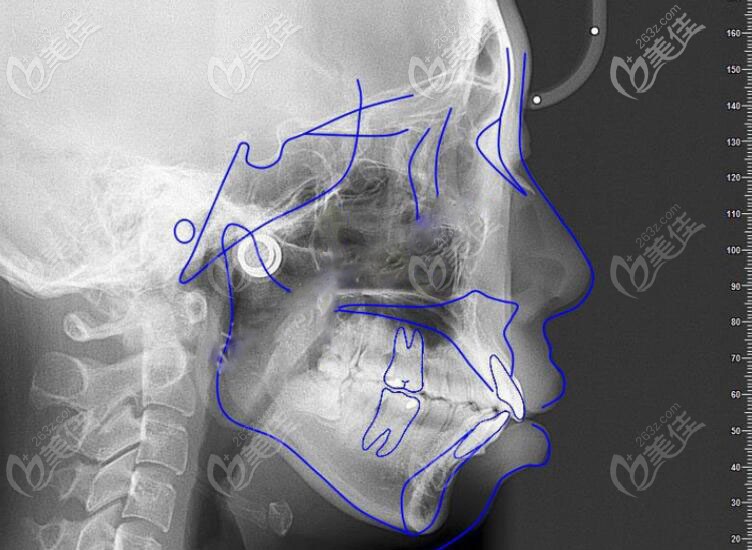

下圖是醫(yī)生用藍(lán)線畫出來顧客的唇側(cè)面貌和牙齒咬合關(guān)系:

當(dāng)時直接考慮的是使用鋼牙套還是隱適美,因?yàn)?strong>顧客還有社交需求,考慮到美觀選擇的隱形矯正器,但是要說的是鋼牙套也是可以達(dá)到矯正效果的哦。